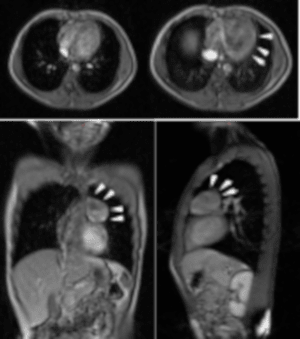

En la Resonancia Magnética de tórax, en planos y secuencias convencionales en equipo GE EchoSpeed 1.5 T se evidencia lesión de ocupación de espacio localizada a nivel del mediastino anterosuperior redondeada, de contornos bien definidos discretamente heterogéneo que mide 4.3 x 5.5 x 5.1 cm, con mínimo realce periférico, que luego de la administración de contraste endovenoso (Gadolinio) con comportamiento predominantemente hiperintenso en secuencias T2 e hipointenso en secuencias T1 cambios que plantean con los antecedentes y la clínica neuromuscular del paciente compatible con miastenia gravis y la presencia de un Timoma (Figura.2).

Figura 2. Resonancia Magnética de Tórax. Se evidencio lesión de ocupación de espacio localizada a nivel del mediastino anterosuperior redondeada, de contornos bien definidos discretamente heterogéneo que mide 4.3 x 5.5 x 5.1 cm, con mínimo realce periférico, que luego de la administración de contraste endovenoso (Gadolinio) con comportamiento predominantemente hiperintenso en secuencias T2 e hipointenso en secuencias T1 (flechas blancas), compatible con timoma.